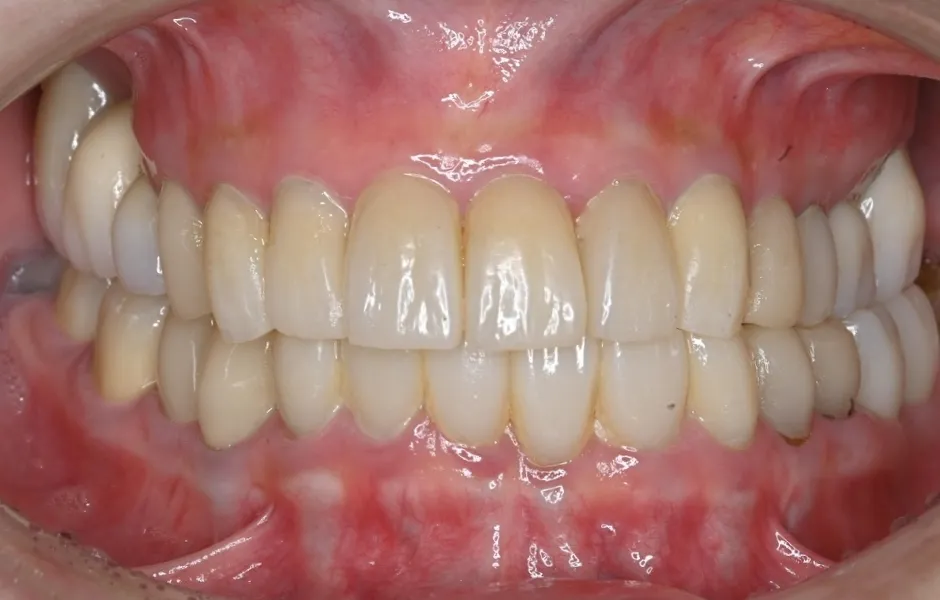

全顎治療・咬合治療

(歯がボロボロ)虫歯や歯周病が悪化して、歯を失っている・ボロボロのまま放置すると、機能性と審美性に影響がでます。お口のトラブルを改善できるよう、さまざまな治療をご提案します。

インプラント治療

失った歯を補う方法の1つで、インプラントが歯根の代わりを果たすことで天然歯に近い噛み心地を再現します。当院ではサージカルガイドを使用することで、より精密な埋入を可能とし、術後の痛みや腫れを軽減しています。機能性だけでなく審美性も回復します。